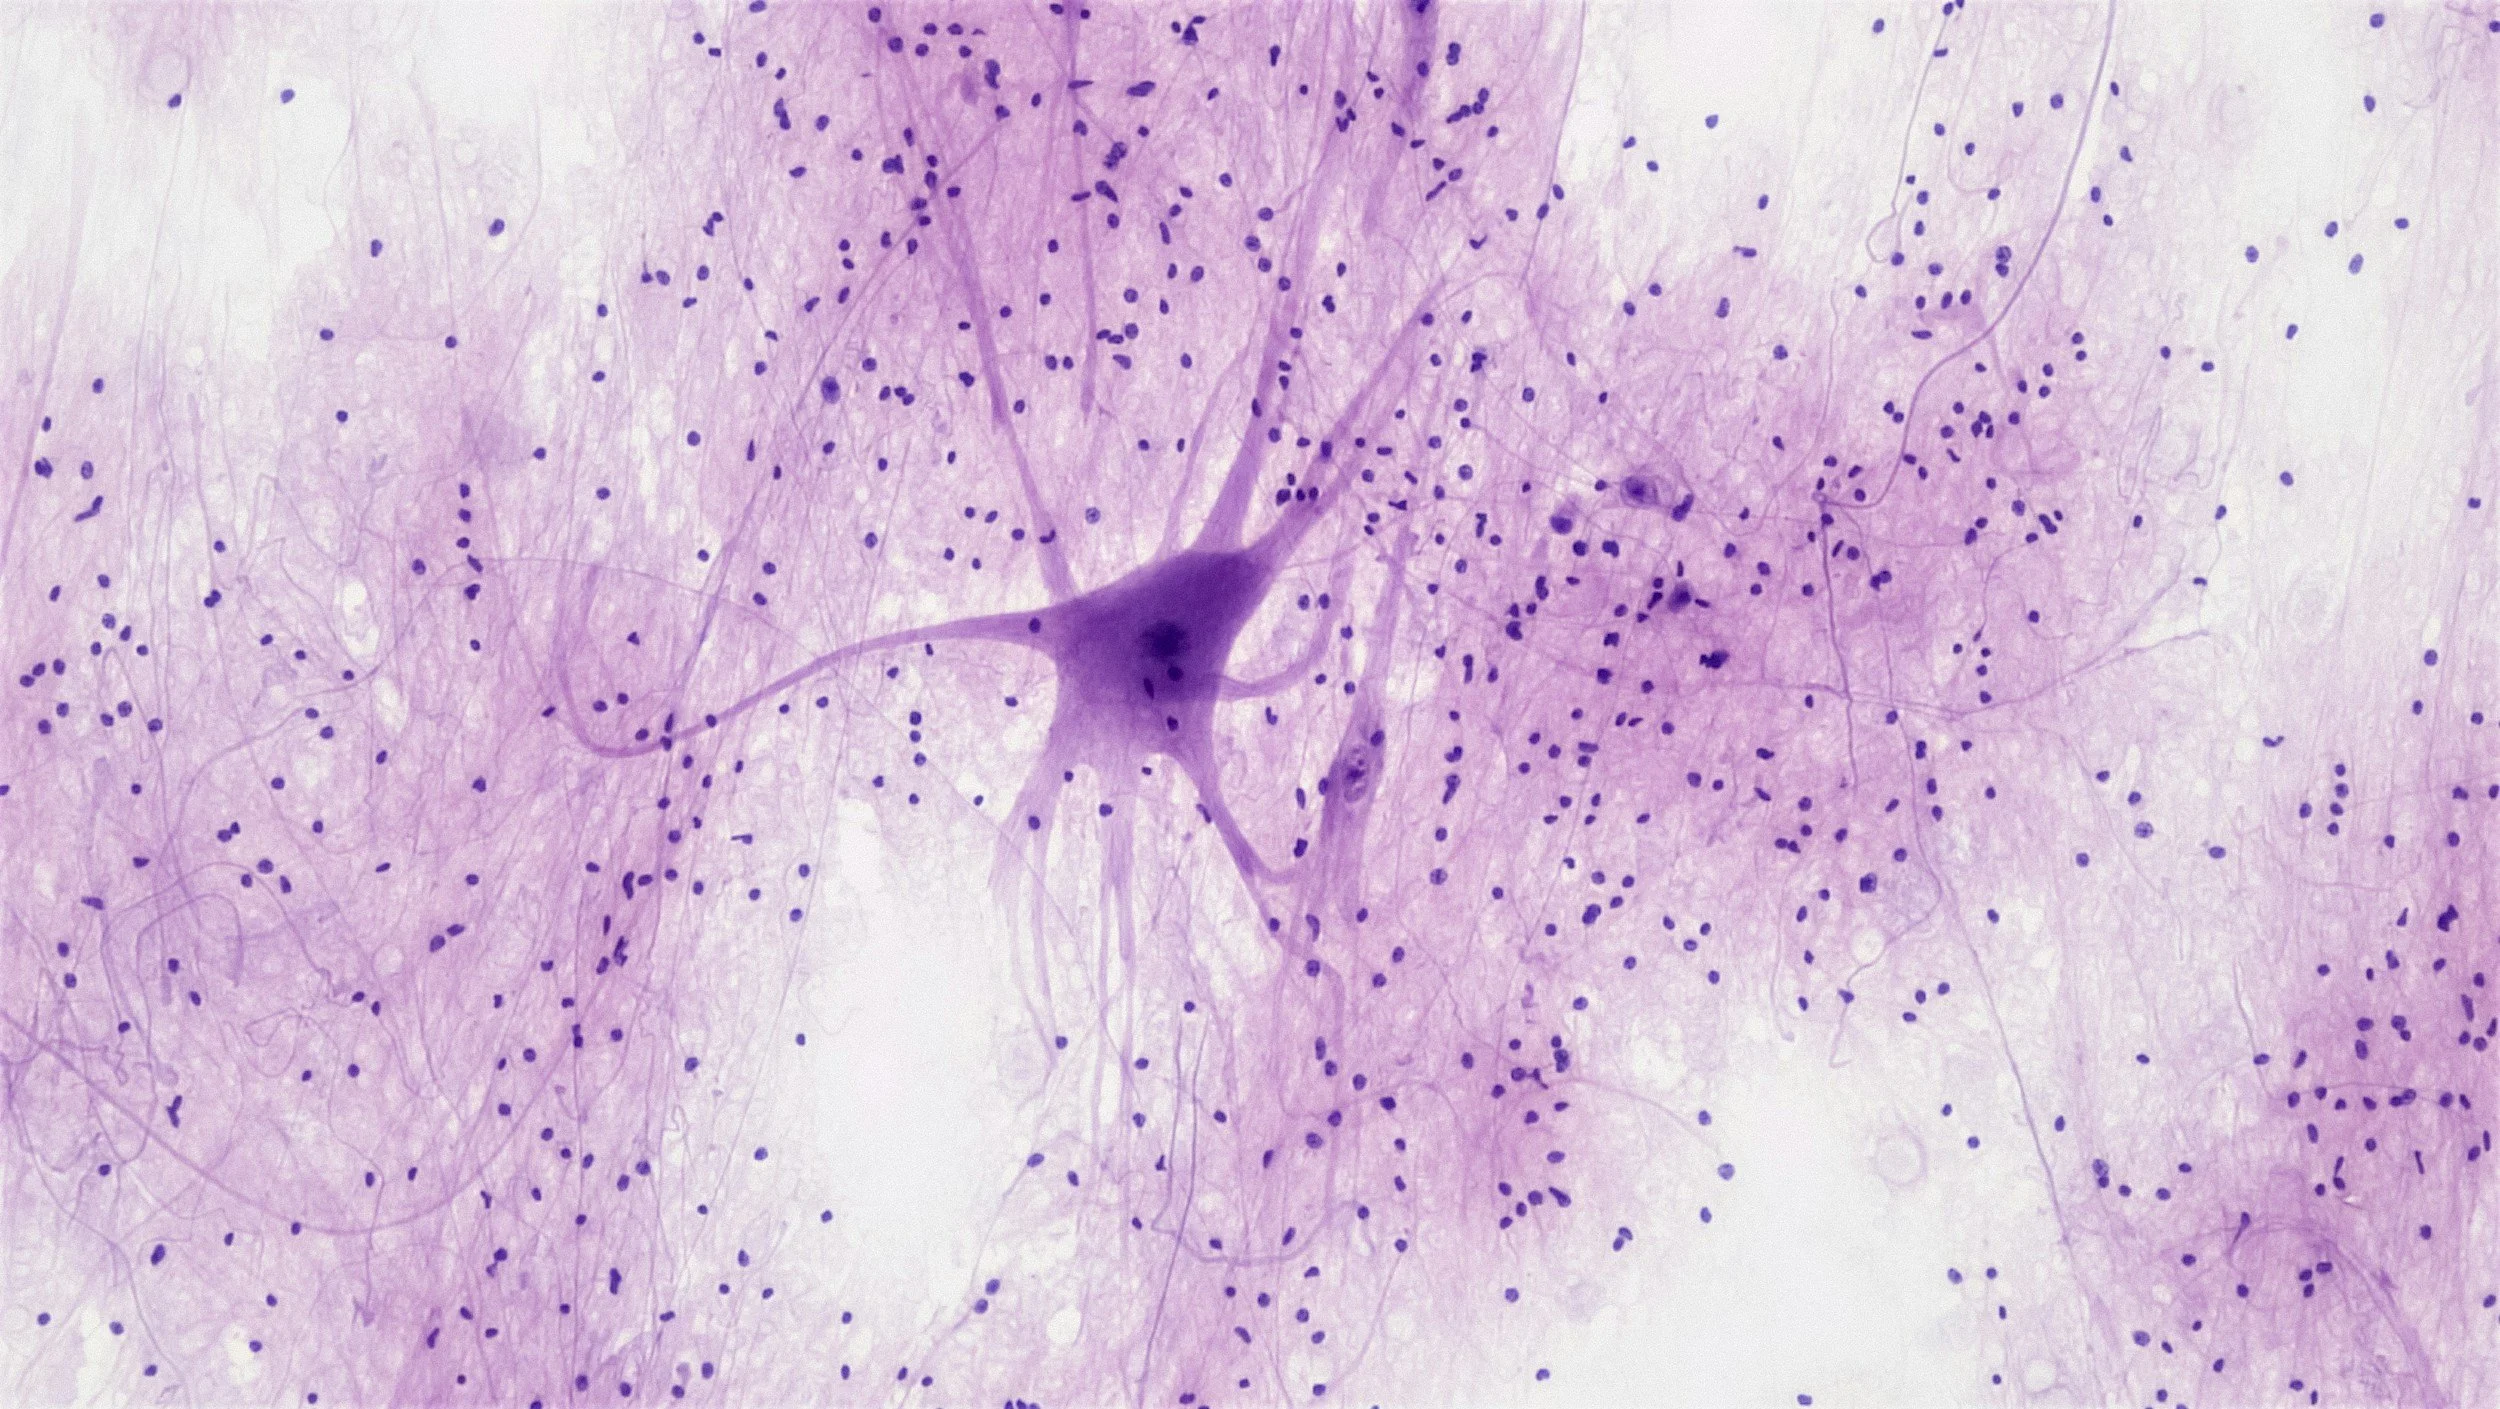

HISTO is designed to give learners a fundamental understanding of histology and a systematic approach to analyzing histology slides using a case-based approach. These skills are essential for medical students, first year pathology residents, and anyone interested in understanding pathology better! Once the course is complete, learners should be able to approach viewing slides systematically, determine normal from abnormal tissue, and describe slides using standard terminology.